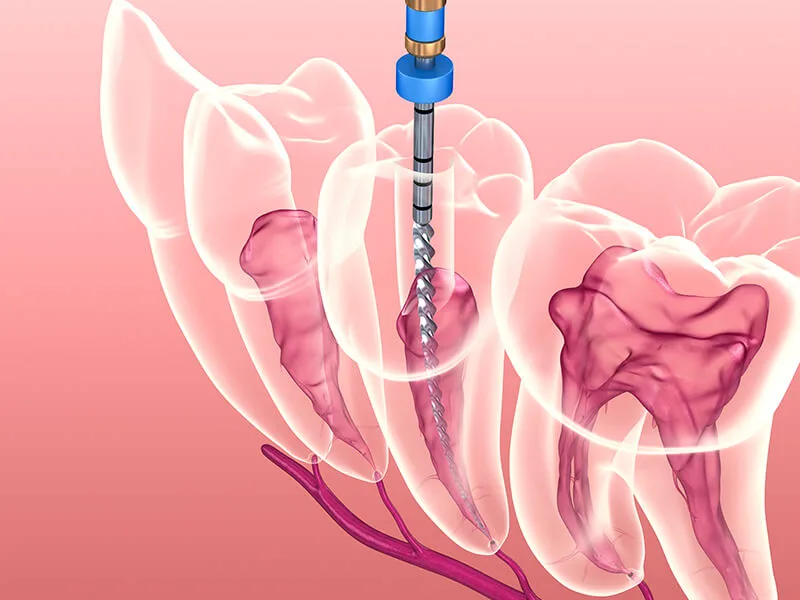

Recursos Técnicos: Uso de instrumentação rotatória e localizadores eletrônicos para maior exatidão;

Sessão de Endodontia: Remoção da polpa, limpeza minuciosa e selamento com materiais biocompatíveis;